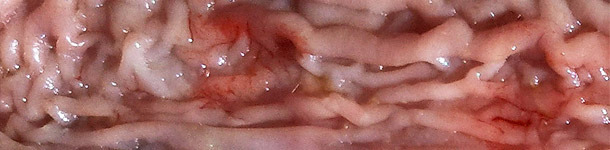

- Engrosamiento de la mucosa en la parte distal del intestino delgado (íleon terminal). Que se presenta rígida y se observa a través de la serosa.

- Ileitis proliferativa en la zona próxima a la válvula ileocecal. Mucosa húmeda con pliegues y muy engrosada.

- Presencia de flecos ligeramente adheridos.